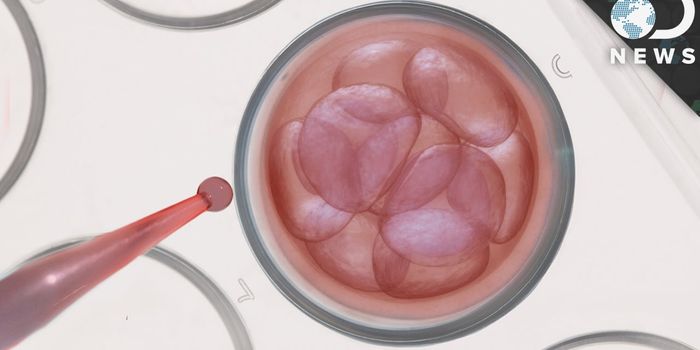

DEC 14, 2017VideosWhen researchers first began to learn more about stem cells, their potential seemed unlimited. But first researchers had ...